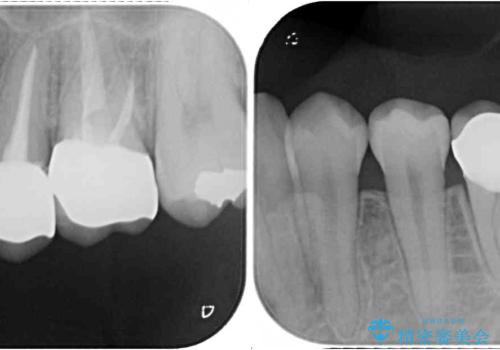

- 下顎の前歯が隠れていることと、デコボコを気にして来院された患者様です。

銀歯やムシ歯処置の必要な歯が奥歯にあり気になっていたので、矯正治療の途中でセラミッククラウンへ変更し、その後歯列を仕上げていくこととしました。

咬み合わせと目立っていた銀歯が改善され、患者様には大変満足していただきました。